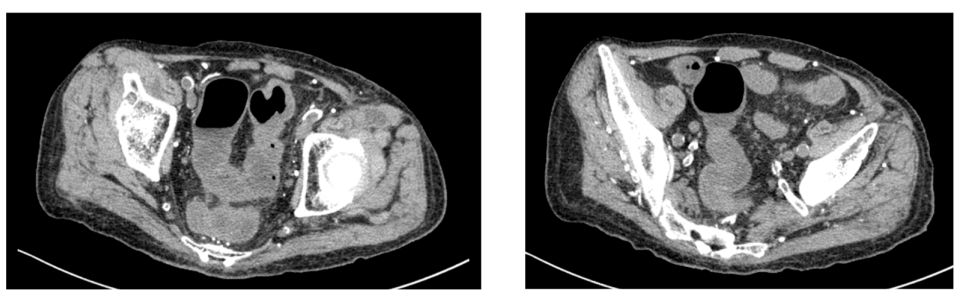

影像学检查:腹部 CT 示结肠壁增厚,符合结肠炎表现(图1)。